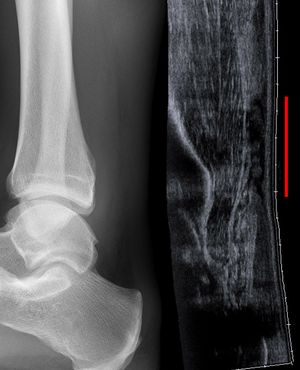

![]() صورة خلفية للقدم والساق، توضح وتر أخيل. | |

صورة خلافية للكاحل البشري، ويشمل وتر أخيل. | |

يمكن أن يستخدم تخطيط الصدى العضلي الهيكيلي لتحديد سماكة الوتر، طبيعته، و وجود تمزق. يتم عن طريق إرسال ترددات صوت عالية شديدة خلال الجسم. تنعكس بعض من هذه الأصوات إلى الفراغات بين السائل بين الخلوي و النسيج الرخو أو العظم. هذه الصور المنعكسة يمكن أن تحلل و تتم حوسبتها إلى صورة. تلتقط هذه الصور في الزمن الحقيقي وتكون مفيدة جداً في تتبع حركة الوتر و تصور الإصابات أو التمزقات المحتملة. هذه الأداة تسهل عملية اكتشاف الأضرار الهيكلية للأنسجة الرخوة، وهي طريقة مناسبة لاكتشاف هذا النوع من الإصابات. هذه الوسيلة من التصوير غير مكلفة، ولا تشمتل على أي إشعاعات مؤينة، وهي موثوقة جداً إذا كانت بأيدي مهرة من أخصائيي تخطيط الصدى.

التصوير الشعاعي يمكن أن يستخدم أيضاً لتعرف انقطاعات وتمزقات الوتر العقبي بشكل غير مباشر. التصوير الشعاعي يستخدم الأشعة السينية لتحليل نقطة الإصابة. لا تكون هذه الوسيلة فعالة جداً في تحديد إصابات النسيج الرخو. تنشأ الأشعة السينية عندما تصطدم الإلكترونات عالية الطاقية بمصدر معدني. يتم الحصول على صور الأشعة السينية من خلال استخدام خصائص التوهين المختلفة للأنسجة ذات الكثافة (مثال: الكالسيوم في العظم) و أنسجة أقل كثافة (مثال: العضلات) عندما تمر هذه الأشعة من خلال النسيج و تلتقط على فيلم. يتم اللجوء للأشعة السينية عامة لتحسين تصور الأجسام ذات الكثافة مثل العظم، و أما النسيج الرخو فيبقى نسبياً غير متمايز في الخلفية. التصوير الشعاعي لديه دور ضئيل في تقييم إصابة الوتر العقبي و ذو فائدة أكثر لاستبعاد الإصابات الأخرى مثل الكسور العقبية.[5]